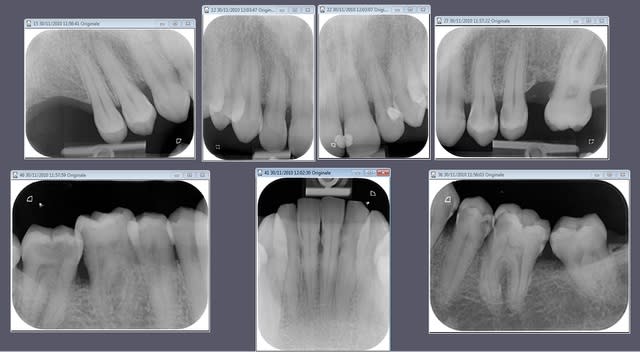

Ci-joint un petit exemple avec le vistascan, je trouve la qualité top, par contre ça irradie plus que la RVG.

Top la qualité !